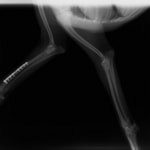

症例3:キルシュナーワイヤーのピンニングによる整復

ペルシャ猫 11ヶ月齢 雄

他院にて左大腿骨遠位の成長板骨折(salter-harrisⅠ型)が認められており、治療相談を目的として来院。当院にて、キルシュナーワイヤーを用いたピンニングにより骨折部位の整復を行いました。術後の経過は良好で、現在も経過観察中です。

術前レントゲン

術後レントゲン